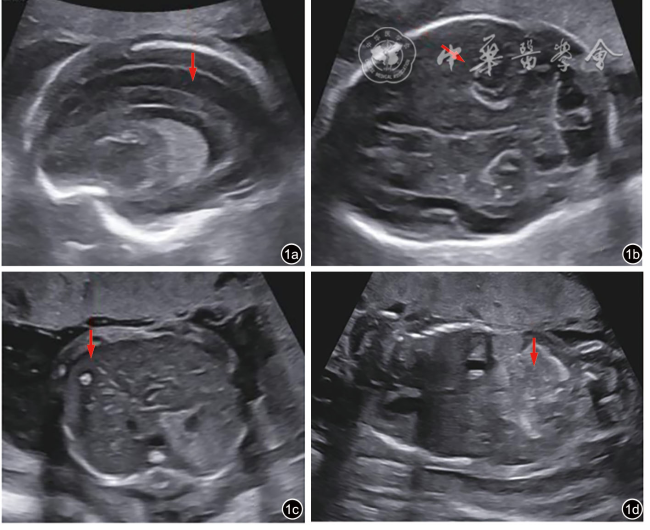

孕妇29岁,孕2产0,孕12周超声检查提示胎儿颈项透明层厚度正常,唐氏综合征筛查及无创胎儿染色体非整倍体检测均为低风险,孕23+1周Ⅲ级超声检查提示胎儿发育异常:胎儿大脑实质板下带与中间带明显分层(图1a),颅内、肝内多发强回声(图1b、1c),肝脾大(肝长径为4.62 cm,对应孕周上限为3.62 cm;脾肋下约0.8 cm),肠道回声增强(图1d),提示宫内感染可能;胎儿体质量数值位于第3百分位数,脐动脉阻力增高、大脑中动脉阻力降低,脑胎盘比<1,羊水少,符合胎儿生长受限(fetal growth restriction,FGR)的诊断。夫妻既往身体均健康,非近亲结婚,否认孕前、孕期毒物与放射线接触史,否认家族遗传病史,孕前致畸五项(风疹病毒、弓形虫、巨细胞病毒、单纯疱疹病毒1型和2型)均阴性。经遗传咨询,行羊膜腔穿刺,结果提示羊水染色体核型及染色体微阵列分析均未见异常,风疹病毒及巨细胞病毒IgM定量检测均为阴性。孕25+3周复查超声提示:胎儿大脑实质板下带与中间带明显分层(图2a),颅内、肝内多发强回声(图2b、2c),肝脾大(肝长径4.29 cm,对应孕周上限为3.94 cm;脾肋下约1.34 cm),心胸面积比增大(图2d)。胎儿体质量数值位于第0.45百分位数,脐动脉阻力增高、大脑中动脉阻力降低,脑胎盘比<1。孕妇加查羊水家系全外显子组测序(whole exome sequencing,WES),结果提示:在RNASEH2A基因上检出2个与胎儿表型相关的意义不明变异,相关疾病为:Aicardi-Goutieres综合征4型,常染色体隐性遗传。经过Sanger测序验证,分别来源于父母。超声已明确胎儿为脑皮质发育畸形(malformations of cortical development,MCD),孕周未满28周,未行头颅MRI检查。由于胎儿并未出生,很多功能学表型无法从宫内抓取,很多表型及影像学特征需要在胎儿出生后体现,如神经系统异常所致的智力残疾,均需要胎儿出生后才能得以验证。但根据现有的影像学结果,胎儿诊断为MCD明确,预后不良可能性大,经过多学科讨论,孕妇夫妻知情选择终止妊娠。本病例报道通过医院伦理委员会批准(KYYS-2025-040)。

图1 孕23+1RNASEH2A基因复合杂合变异胎儿超声图像。图a示胎儿大脑实质板下带与中间带明显分层,图b示颅内多发强回声,图c示肝内多发强回声,图d示肠道回声增强